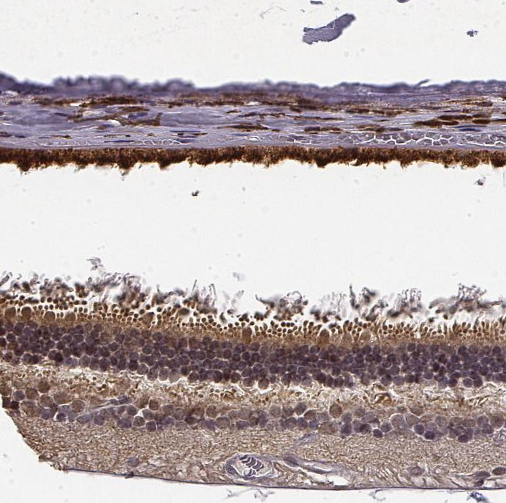

Immunohistochemical staining of human eye, retina shows moderate cytoplasmic positivity in ganglion cell layer and photoreceptor layers.